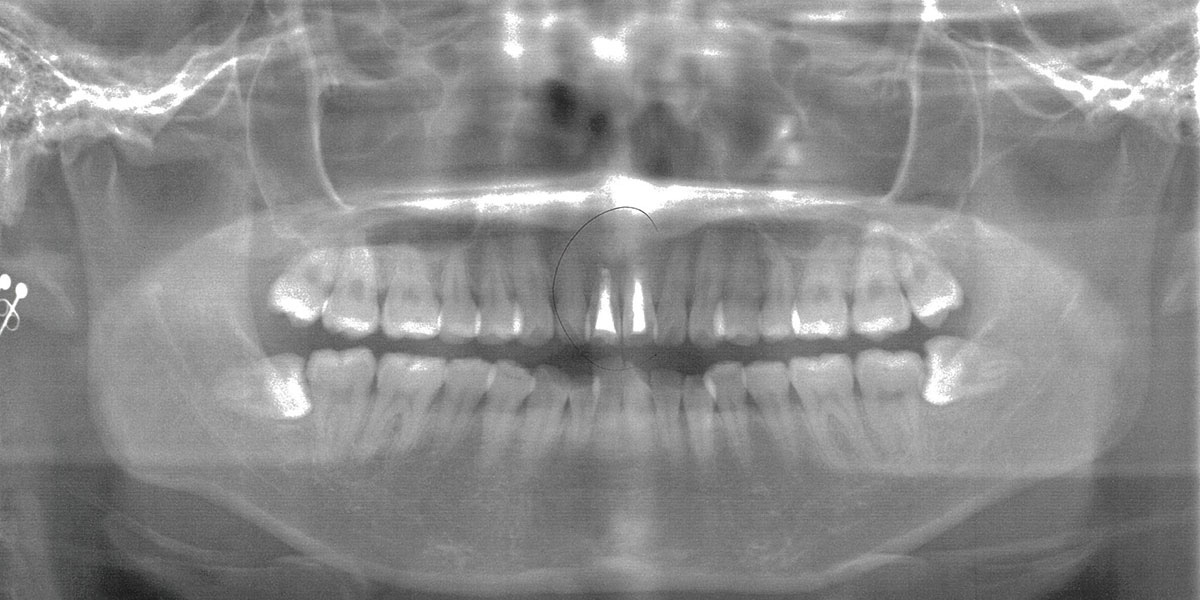

■ レントゲン(治療前)